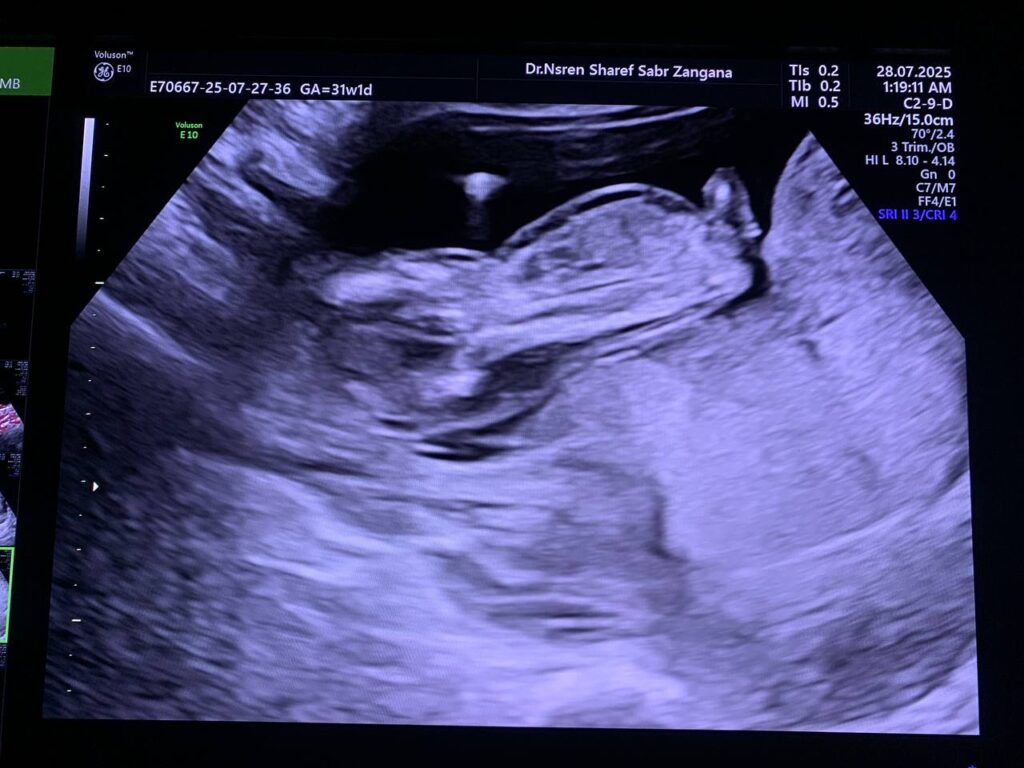

Diffuse edema with Increase nuchal translucency 6.7mm , hypoplastic nasal bone , picture mostly of hydrops fetalis with chromosomal anomaly , please for further study

CRL= 12w+6d